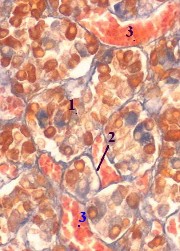

Перечень компонентов. В передней доле имеются три тканевых элемента: секреторные клетки (1) (клетки железистого эпителия), соединительнотканная строма (2) и многочисленные синусоидные (т.е. очень широкие) капилляры (3). Секреторные клетки. а) Секреторные клетки лежат группами, называемыми аденомерами. б) Аденомеры формируют тяжи, складывающиеся в разветвлённую сеть Строма образована прослойками рыхлой соединительной ткани, которые разделяют аденомеры. | 2,б. Препарат – гипофиз человека. Окраска смесью Маллори по Генденгайну. (Среднее увеличение) Полный размер |

22.2.2.3. Передняя доля гипофиза:

тинкториальные типы железистых клеток